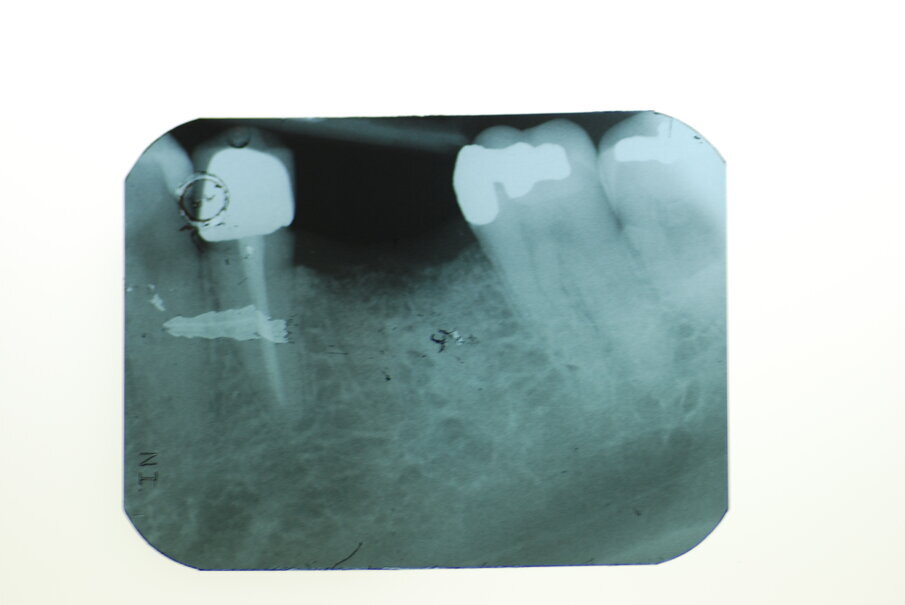

Sei mesi dopo i pazienti sono stati sottoposti ad intervento chirurgico per il posizionamento dell’impianto. Eseguita l’anestesia locale e scollati i lembi a spessore totale in mandibola, è stata eseguita una carotatura per l’analisi istologica della qualità dell’osso (Figg. 4, 5). Nello stesso sito, dopo averlo adeguatamente preparato è stato posizionato un impianto DAE 4 x 11,5 mm al livello dell’osso crestale (Fig. 6). Successivamente sono stati suturati i lembi (Seta, Ethicon 4.0, Johnson & Johnson Medical, New Brunswick/NJ, USA). Infine, prescritti un antinfiammatorio (Nimesulide 100 mg, 2 volte al giorno per 3 giorni), un analgesico (Paracetamolo 500 mg, 1 compressa ogni 8 ore per 3 giorni), e clorexidina 0.12% durante la fase post-operatoria insieme a istruzioni complete all’igene orale. La sutura è stata rimossa a 10 giorni dall’intervento chirurgico. Sei mesi dopo, l’impianto è stato protesizzato con una corona singola avvitata in metallo-ceramica. A 3 mesi e a 3 anni sono state eseguite le radiografie periapicali parallele.

La radiografia eseguita immediatamente dopo il posizionamento dell’impianto ha mostrato che gli impianti dentali erano perfettamente posizionati a livello dell’osso crestale (Fig. 6). Le analisi istologiche della carotatura di osso prelevato hanno mostrato che a 6 mesi dall’intervento di conservazione dell’alveolo, si è formato nuovo tessuto osseo vitale e sono ancora presenti granuli del biomateriale utilizzato (Fig. 12). Il follow up radiografico a 3 anni indica una situazione ossea invariata con l’impianto ancora a livello dell’osso crestale. La parte protesica ancora in buone condizioni senza segni d’infiammazione, né si sono riscontrate mucositi o perimplantiti. I restauri privi di complicanze tecniche.